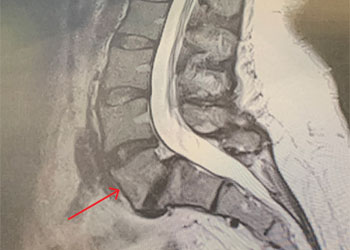

Thoracic Spinal Cord Tumor Case Presentation

Author: Xavier P. J. Gaudin D.O., F.A.C.O.S., Read More!